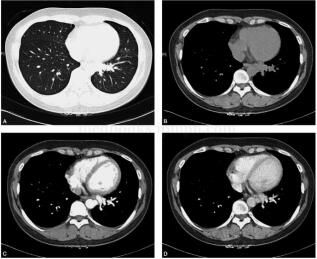

患者女,36岁,自3年前出现发热、咳嗽,时有血痰,无发热及胸闷气短,多次按炎症治疗,抗炎后略好转,入院后再次行CT检查,提示左肺下叶肿块合并阻塞性肺炎,抗炎治疗后炎症略吸收,后行增强CT检查,示左肺下叶基底段病变内来自降主动脉到病灶的异常血管,行左肺下叶切除术,术后恢复良好(图1)。

图1 肺窗示左下叶内基底段支气管周围可见不规则高密度影,边界不清楚,与周围血管及支气管分界不清,周围未见毛刺及胸膜牵拉,其远端见少许斑片影。纵隔窗示左下肺后基底段不规则团块影,呈软组织密度,其内密度较均匀,紧贴后纵隔降主动脉旁。动脉期病变内见多发迂曲的血管影,于第10胸椎水平自降主动脉左侧缘发出一异常血管分支,先向前下随后返折向后上,继而呈水平位向外行走于左下肺静脉后方。静脉期显示左下肺静脉回流。